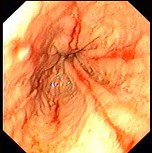

(单选题)胃镜检查如下图,诊断为()。

A:食管癌

B:反流性食管炎

C:心绞痛

D:消化性溃疡

E:贲门癌